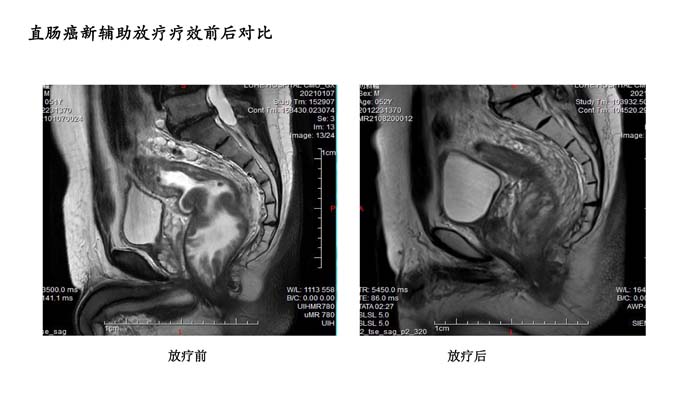

直肠癌新辅助放疗疗效前后对比4

- 直肠癌新辅助放疗疗效前后对比4